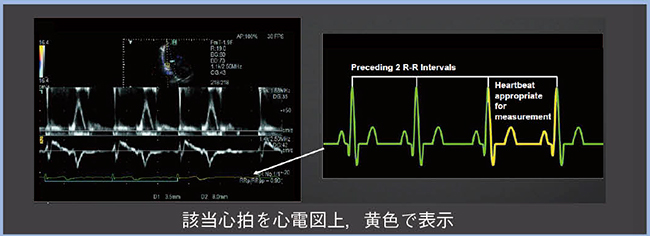

心房細動における心機能評価に当たっては,先行R-R間隔(RR1)と先々行R-R間隔(RR2)の比(RR1/RR2)がほぼ1となる区間を評価心拍としてエコー指標を評価すると,複数心拍で評価した値と良好な相関が得られる(図3)。これが,index beatという考え方であり,index beatを自動で簡便に検出する機能がR-R Navigationである。検出されたindex beatは心電図上,黄色で表示され(図4),その心拍を用いることで,心房細動の心機能評価においても再現性良くエコー指標を計測することができる。また,index beatは自動検出されるため,解析時間の短縮にもつながる。

図4 R-R Navigationによるindex beatの自動検出